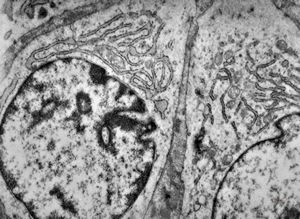

F,25y. | myopathy - atrophic and regenerating muscle cells

M,2y. | myopathy - regenerating muscle cell